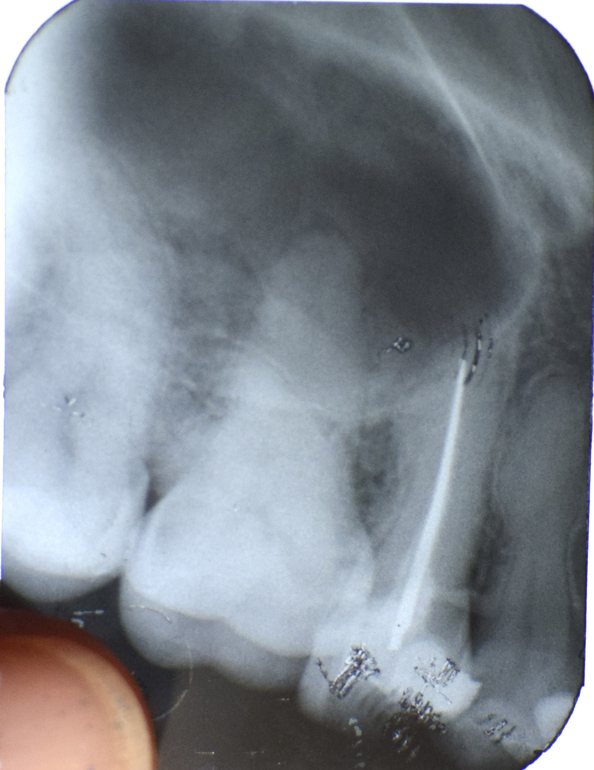

Здравствуйте! Месяц назад я лечила верхний 6 зуб, стоматолог сказала, что полость очень большая, но получилось обойтись пломбой. С тех пор зуб ноет, 2 недели после лечения довольно сильно, помогал Найз (1-2 таблетки в день), сейчас меньше, но до сих пор при боли принимаю Найз, (другой врач сказал что расширение канала, но решил не трогать, к чему это может привести) рядом депульпированный зуб травмировал десну кусочком материала, его поправили 1 неделю назад, теперь в области 5, 6, 7 зубов с внутренней стороны болит и воспаляется десна. Подскажите, нужно ли депульпировать 6 зуб, не начала ли там образовываться киста. И что делать с десной? (десна сегодня получше, промывала мирамистином) Снимок прикрепляю. Проверяли на ЭОД, показатель 12-13 (сказали что это кариес, а не пульпит) Спасибо